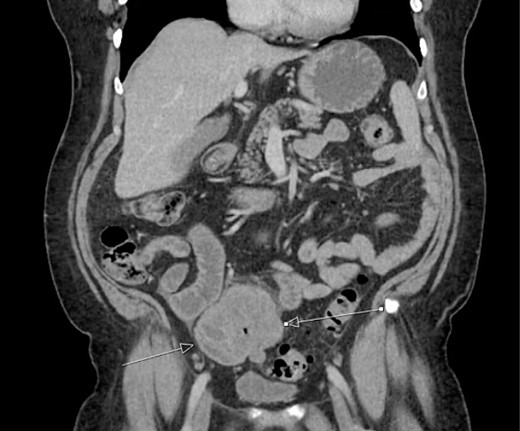

The patient was initially managed nonoperatively with conservative measures including nasogastric (NG) tube decompression, pain control, and serial abdominal exams. Surgery was consulted once CT imaging was obtained (Figs 1–3) and recommended that the patient undergo surgery to resect the identified mass and relieve the obstruction. During the surgical exploration, a mass originating from the terminal ilium was identified that was densely adhered to the peritoneum, bladder, and sigmoid colon, requiring careful dissection. The mass, three lymph nodes, and 29 cm of associated small bowel segment was resected with grossly negative margins, with the mass measuring 7 cm × 8 cm × 9.5 cm. A side-to-side anastomosis was created and the specimens were sent to pathology for further investigation. Postoperatively the patient was hospitalized for 7 days for pain control and monitoring. On postoperative day eight he was discharged with follow up appointments with oncology, general surgery, and a referral to an academic cancer center.

Initial CT imaging, sagittal cut, showing necrotic mass causing small bowel obstruction.